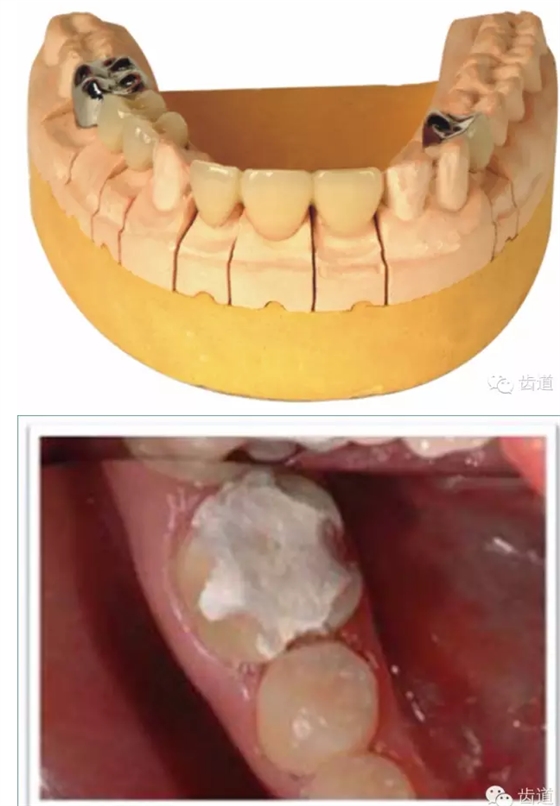

牙體預(yù)備時(shí)應(yīng)考慮的問題

l保護(hù)牙體組織

l基牙具有良好的固位形

l基牙具有良好的抗力形

l預(yù)留修復(fù)體的空間

l邊緣的適合性

l保護(hù)牙周組織

l多個(gè)基牙時(shí)就位道的調(diào)節(jié)

l實(shí)際備牙產(chǎn)生的問題

1. 保護(hù)牙體組織

l防止過度預(yù)備(造成牙髓激惹)

l保留活髓(保留牙體的整體性和韌性)

l過度預(yù)備抗力形喪失

2. 基牙具有良好的固位形

摩擦力

正壓力:即修復(fù)體的密貼程度(小于0.2mm)

表面粗糙程度

牙的外形及洞形的幾何形狀:主要是牙體制備出一定聚合角度產(chǎn)生的阻擋作用